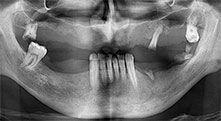

Pourriez-vous décrire brièvement par exemple comment vous procédez pour mobiliser les blocs osseux en vue d’une greffe ?

Pr Bratu : Nous préférons prélever l'os sur la crête oblique externe de la mandibule postérieure, et non dans la région interforaminale. Après l'incision des tissus mous, nous utilisons les nouvelles scies pour définir la quantité d'os à prélever. De la même manière, nous les utilisons également pour la totalité de la préparation dans presque 80 % des cas. Nous avons également parfois recours à d'autres instruments piézoélectriques et, pour terminer, à un burin pour mobiliser le bloc. Nous trouvons cette technique chirurgicale très efficace.

Pr Bratu : J'estime que la chirurgie piézoélectrique a fait faire un grand bon en avant à la chirurgie orale. Grâce à cette technique, la préparation osseuse est plus sûre et plus facile. Par exemple, les extractions entraînent une perte osseuse minime. C'est très important d'un point de vue esthétique, surtout si la pose d'implants est prévue immédiatement.